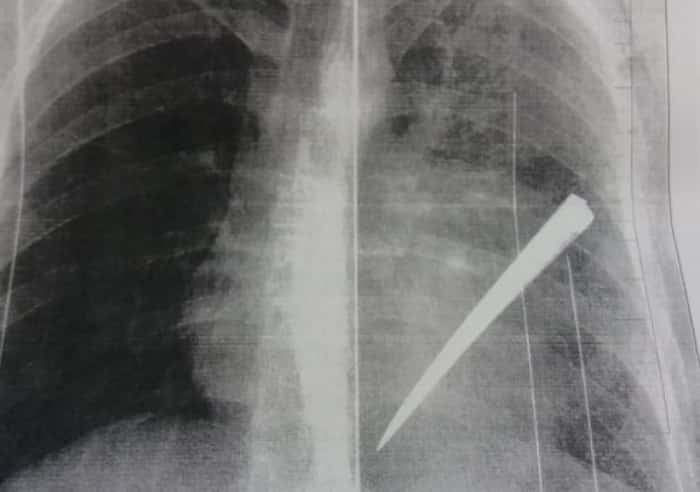

Na tarde da quarta-feira, 13, a Polícia Civil, através da Delegacia de Itaguatins, prendeu preventivamente Symon Maxuell dos Santos Silva, 26 anos. Ele e seu comparsa Igor Santos Matos, 22 anos, que também se encontra preso preventivamente, são acusados de tentar matar, a facadas, William Lourenço de Sousa, 24 anos, após uma festa no município de Itaguatins, no Bico do Papagaio, no dia 18 de outubro de 2018. Um pedaço da lâmina chegou a ficar dentro do corpo da vítima.